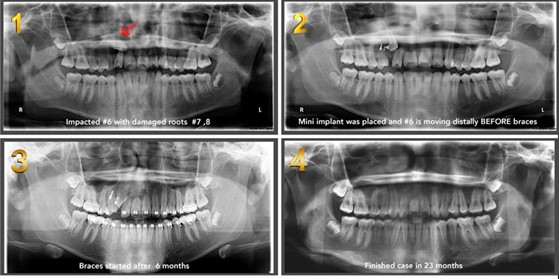

4. Close the space of a missing tooth.

Missing teeth are associated with a different degree of bone loss. This bone loss will place a challenge to replace the missing tooth with a traditional dental implant. Another alternative to the dental implant is to close the space with braces if enough teeth exist. This technique will require the use of a Temporary anchorage device TADS to direct the force into the direction of the missing tooth. Make sure the root size of the moving tooth is strong enough “conical roots in molars perform weakly in bodily movement”